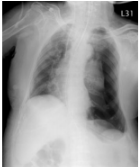

37. 小雄為足月新生兒,出生後出現呼吸窘迫及發紺、胸部較為突出,聽診時右側呼吸音 及心音較左側清楚,X 光如下圖,下列診斷何者最為可能?(A) Left pneumothorax(B) Dextrocardia(C) Left diaphragmatic hernia(D) Tracheoesophageal fistula